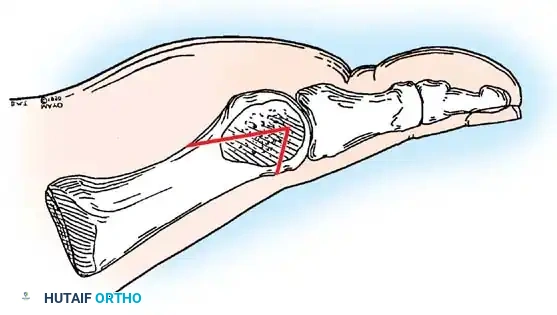

Keller Resection Arthroplasty The Keller procedure combines resection hemiarthroplasty of the fi rst metatarsophalangeal joint with removal of the medial eminence of the fi rst metatarsal (Fig. 78-28). Although removing the base of the proximal phalanx decompresses the joint and mobilizes the hallux, allowing marked correction of valgus, the varus of the fi rst metatarsal is not corrected, and maintaining correction of the valgus of the hallux is diffi cult. Other complications of the Keller procedure have been emphasized in the literature to such an extent (with neither the incidence nor the severity of such complications clearly documented) that the indications for this procedure have been limited severely. In our experience, however, complications are uncommon if patients are selected carefully. Modifi cations in the original technique also have allowed expansion of the indications for the Keller bunionectomy. Candidates for the Keller procedure are patients older than 50 years with moderate-to-severe hallux valgus (30 to 45 degrees); intermetatarsal angles of 13 degrees or less, indicating mild-to-moderate metatarsus primus varus; and pain over the medial eminence with any shoe worn, so the variety of shoes the patient can wear is severely limited. An incongruous fi rst metatarsophalangeal joint caused by

• Resect the medial eminence at the sagittal groove, beginning dorsally at its distal edge and directing a 9-mm oscillating blade

(or osteotome) plantarward and slightly medially (5 to 10 degrees).

• Remove the base of the proximal phalanx at the metaphysealdiaphyseal junction, which usually constitutes the proximal third of the phalanx (Fig. 78-30A and B). To prevent damage to the fl exor hallucis longus and the neurovascular bundles, place a retractor over the bone dorsally and plantarward, and rotate the phalanx into view. Also, do not allow the saw blade to exit bone more than 1 to 2 mm.

• When the osteotomy has been completed, grasp the basilar fragment with a small Kocher clamp or towel clip, and rotate the fragment while applying medial pull to excise it. Lift it away from its lateral attachments, which are primarily the lateral collateral ligaments and the adductor muscle tendinous insertion (Fig. 78-30C).